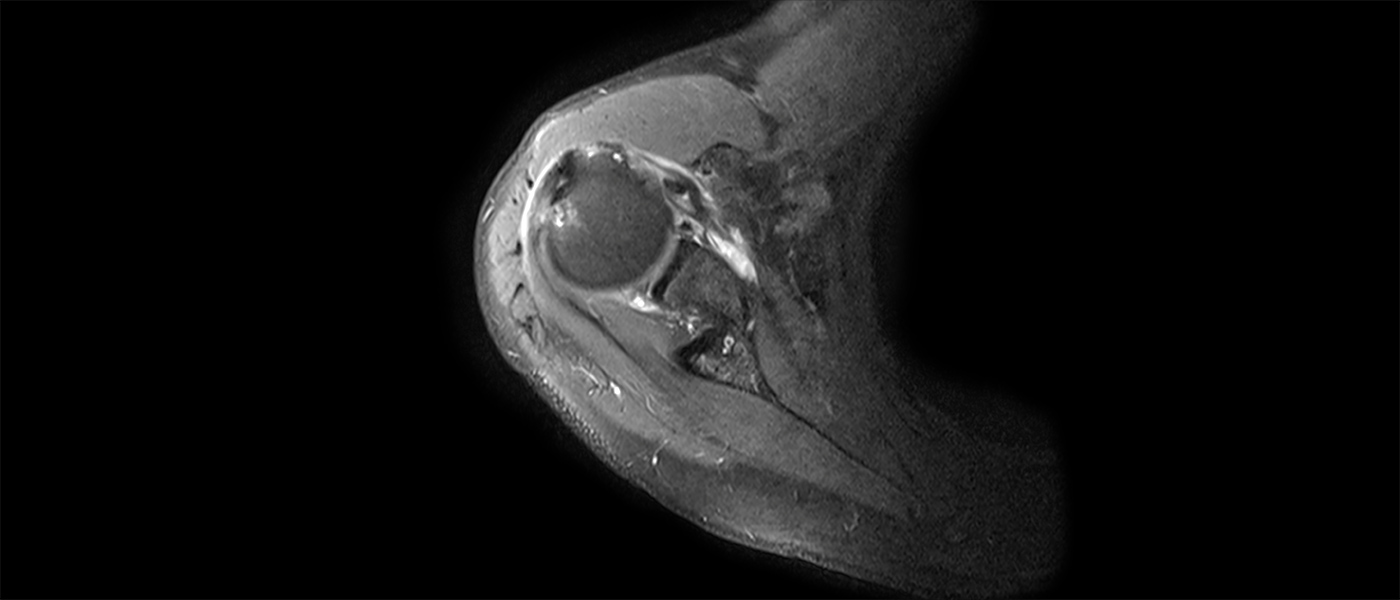

- Arthroscopic Management of Rotator Cuff Tears

- Arthroscopic Management of Glenohumeral Instability

Learning objectivesUpon completion of this event, participants will be able to Identify shoulder anatomy and pathology related to sports and soft-tissue injuries Obtain an injury-specific history and perform a detailed physical exam of the shoulder Interpret appropriate radiographic images Create an accurate diagnosis Describe the treatment options and select an appropriate plan Perform arthroscopic and/or open procedures based on best scientific guidelines Develop an appropriate postoperative rehabilitation plan Identify and manage potential intra- and postoperative complications Review common, difficult, failed, and revision cases and explain how to manage poor outcomes